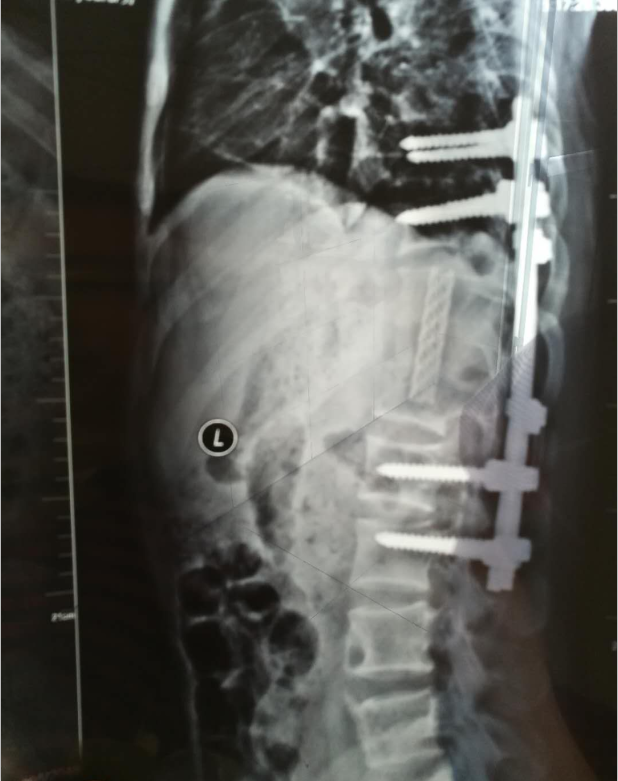

住院后,張勇組織科室醫(yī)務(wù)人員對(duì)小強(qiáng)的病情進(jìn)行了多次詳細(xì)的研究討論,反復(fù)斟酌,最終制定出了一個(gè)科學(xué)的手術(shù)方案。516日,經(jīng)過(guò)6個(gè)多小時(shí)的手術(shù),患者手術(shù)順利完成,手術(shù)中放出膿液近2000ml,死骨得到徹底清除,脊柱重穩(wěn)定。手術(shù)后患者精神明顯恢復(fù),食欲恢復(fù)正常,性格也開(kāi)朗起來(lái)。65日,患者康復(fù)出院。

術(shù)后